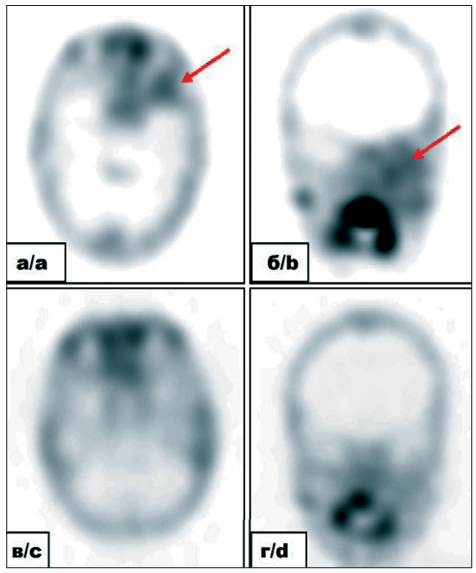

1. Рис. 1. Собственные результаты томосцинтиграмм головного мозга с 99mTc-пертехнетатом пациентки П. с диагнозом: Альвеолярная рабдомиосаркома параменингеальной локализации с интракраниальным распространением, лептоменингеальные метастазы в головном мозге, стадия IV (T2вN0M1. IRS IVa). На томограммах в аксиальной (а) и фронтальной (б) проекциях до начала лечения определяется очагово-повышенное распределение РФЛП в проекции первичной опухоли параменингеально слева (общий носовой ход, верхнечелюстная пазуха, левая орбита и средняя черепная ямка) – красные стрелки. Признаки поражения «по контакту» оболочек головного мозга в области средней черепной ямки слева. При контрольном исследовании после 9 курсов химиотерапии, 6 курсов интратекальной химиотерапии, лучевой терапии в объеме краниоспинального облучения (СОД 36 Гр), на область первичного распространения опухоли (СОД 50,4 Гр) по протоколу CWS 2014 (группа метастатических сарком): на томограммах в аксиальной (в) и фронтальной (г) проекциях определяется незначительно повышенное распределение РФЛП в проекции первичной опухоли параменингеально слева. По сравнению с инициальным исследованием отмечается выраженная положительная динамика. Примечание: рисунок выполнен авторами